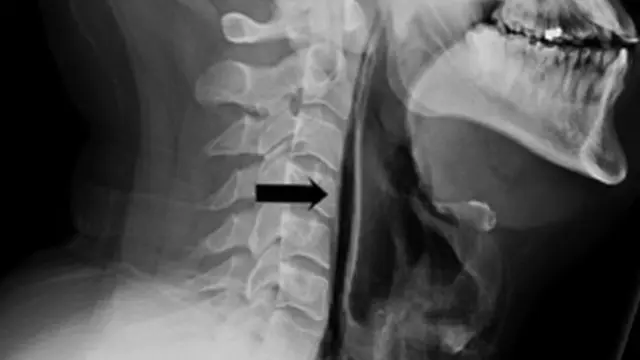

ผลการตรวจเอกซเรย์พบว่า มีอากาศรั่วไหลออกจากหลอดลมคอ (Trachea) ซึ่งเป็นอวัยวะส่วนที่บางครั้งเรียกกันว่าท่อลม (Windpipe) โดยอากาศออกมาจากรอยฉีกขาดและเข้าไปในเนื้อเยื่ออ่อนโดยรอบ

ที่มาของภาพ, BMJ